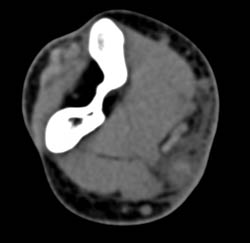

GSW Pelvis With Bleed